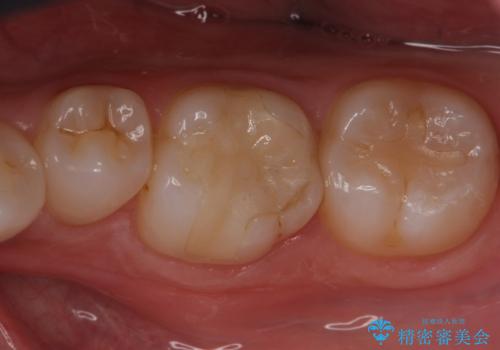

e-maxインレーにて治療しました。

白い詰め物が入り、ザラザラもなくなりました。

一つ手前の古いプラスチックで治療されている歯も現在詰め物にやりかえを検討中です。